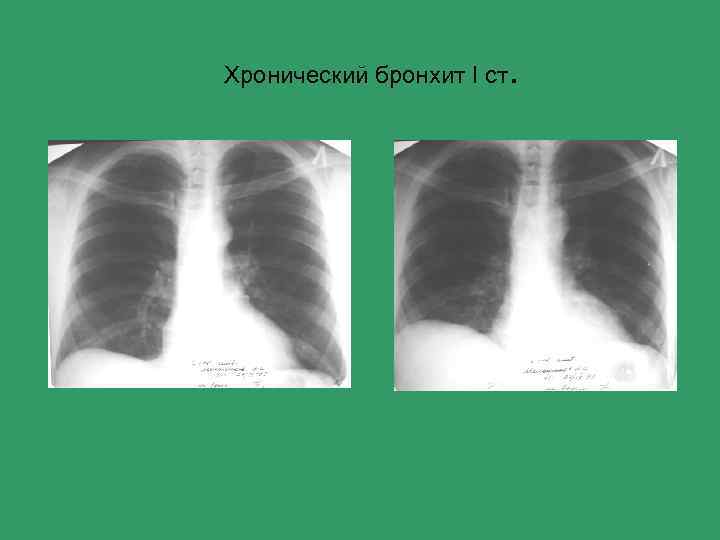

Хронический бронхит I ст .